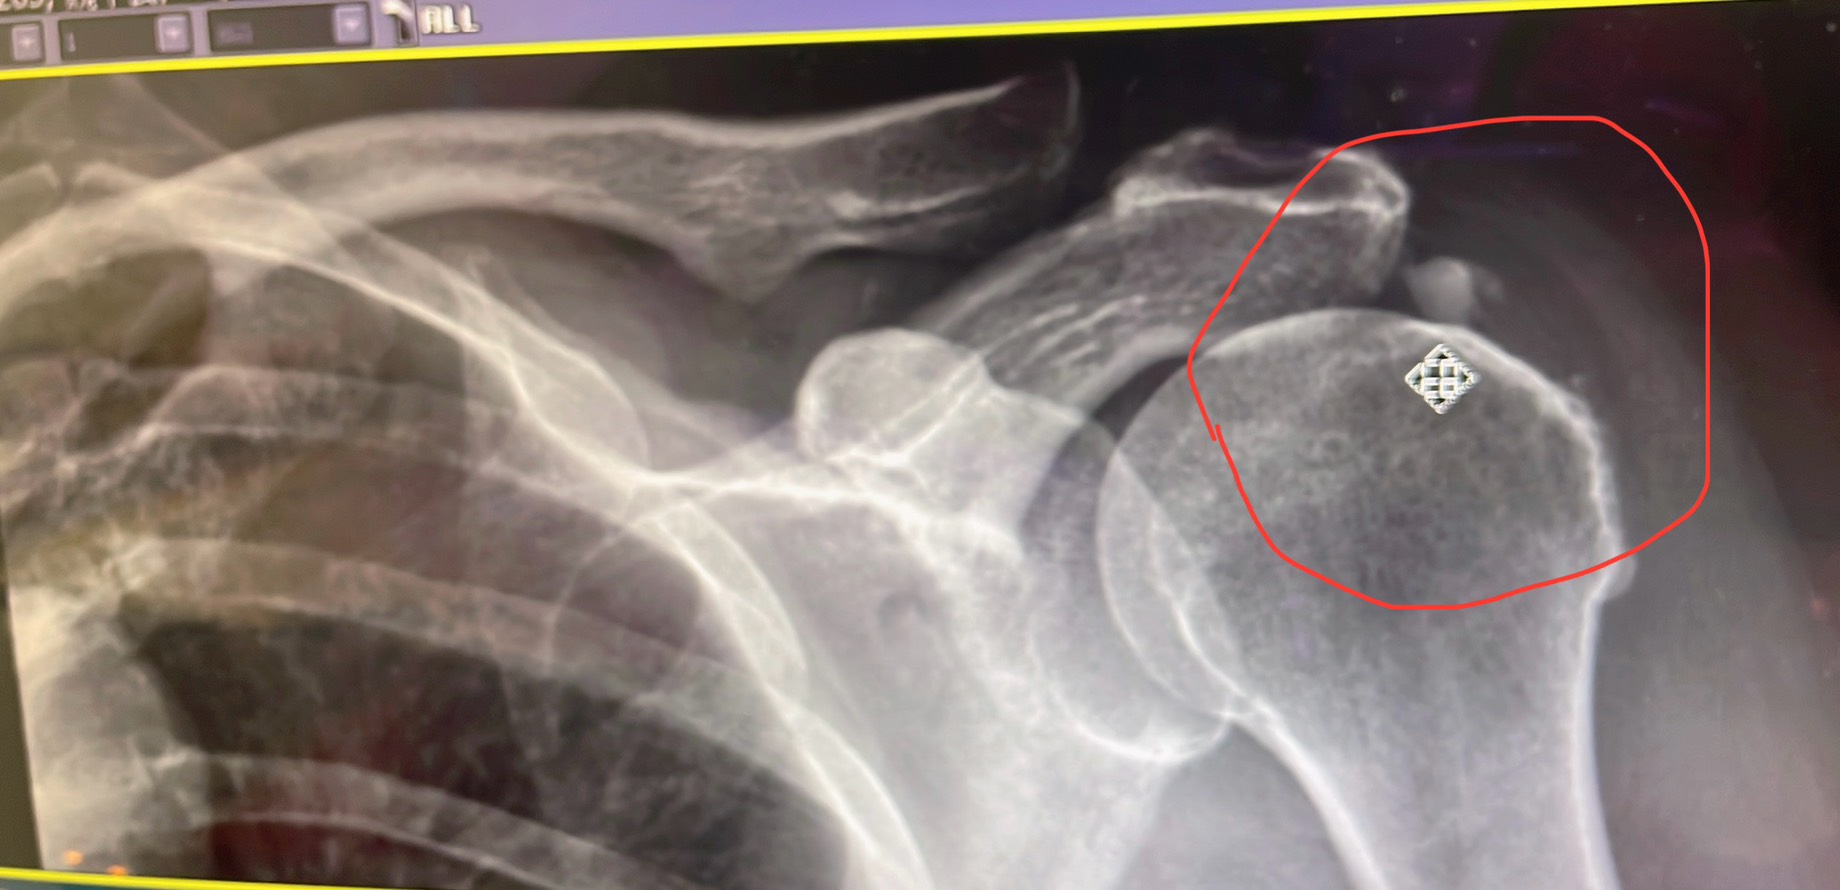

透過高能量壓力波,直接對準深層的鈣化沉積物進行「拆解」,讓身體自然吸收,告別頑固痛點。